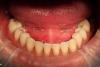

Bobby Опубликовано 22 июля, 2013 Автор Поделиться Опубликовано 22 июля, 2013 Временные конструкции делались с опорой на постоянные импланты? да В данном случае установка нижних имплантатов была одномоментно с удалением почти всех нижних зубов. Была осуществлена немедленная нагрузка. На верхней челюсти практически также. Но не все имплантаты участвовали в немедленной нагрузке, что-то было ушито (с) FB Ссылка на комментарий